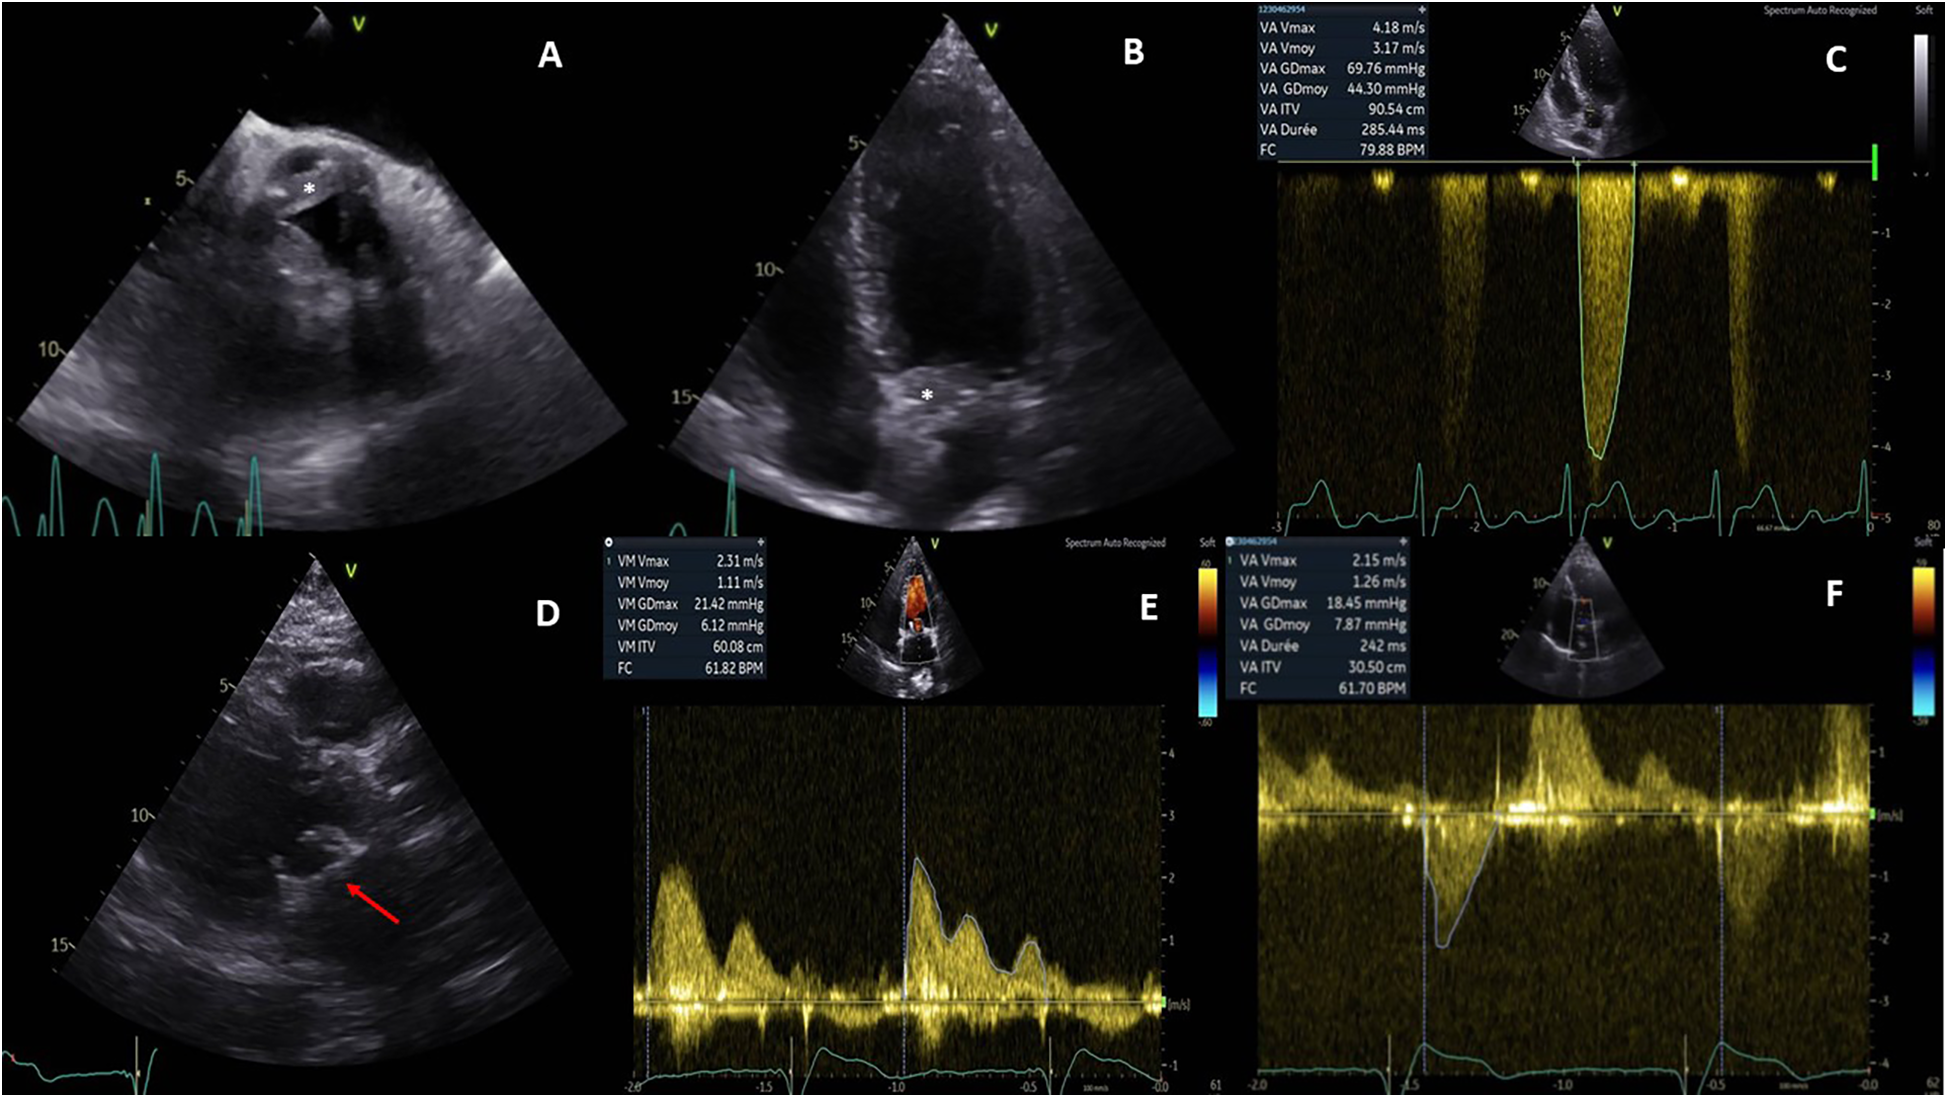

Initial electrocardiogram (ECG) showed sinus rhythm with right bundle branch block and left anterior fascicular block. Holter monitoring revealed paroxysmal complete AVB lasting 8 s. Transthoracic and transesophageal echocardiography revealed preserved left ventricular ejection fraction (LVEF, 68%), moderate aortic regurgitation, and significant thickening of the aortic valve extending to the aorto-mitral curtain and anterior mitral valve (Figures 1A,B), causing LVOT obstruction with maximal and mean gradient of 70 and 44 mmHg (Figure 1C), respectively. Computerized tomography (CT) confirmed hyperplasic tissue at the LVOT (Figures 2A,B). Coronary angiography showed normal results. Laboratory tests showed mild leucocytosis (135 000/ml), slightly elevated C-reactive protein (12 mg/L), and NT-pro brain natriuretic peptide (295 pg/ml); troponin level was normal.

Figure 1

Pre- and postoperative echocardiography. Preoperative echocardiography showed an abnormal thickening of aortic cusps (*, A) extending to the anterior leaflet of the mitral valve (*, B) and resulting a significant subaortic obstruction (maximal gradient of 70 mmHg, C). Postoperative echocardiography demonstrated a well-positioned mitral bioprosthesis (arrow, D); the mean transprosthetic gradient was 1.1 mmHg (E) in the mitral position and 7.8 mmHg (F) in the aortic position.

The postoperative course was uneventful, and the patient was discharged on day 10. Echocardiography showed well-functioned aortic and mitral prostheses (Figures 1D–F); electrophysiological control of epicardial electrodes and pacemaker was normal. A pathological examination revealed lymphoplasmacytic infiltration and IgG4+/IgG+ cell ratio of 30%–50% (Figures 2C,D), suggesting IgG4-RD.